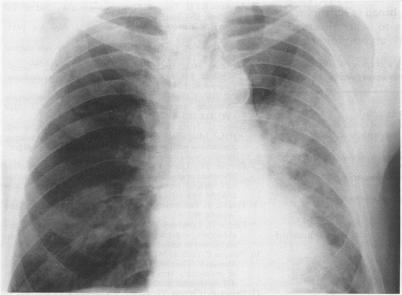

Cryptogenic organising pneumonitis (bronchiolitis obliterans organising pneumonia) is an uncommon condition that often responds to steroids. It is characterised clinically by constitutional symptoms, pathologically by intra-alveolar organising fibrosis, and radiologically by patchy pulmonary infiltrates. Its full clinical spectrum and course are only partially described and understood. Six patients are described, seen over three years, with considerably diverse clinical and radiological presentations (two had diffuse lung infiltrates, two had peripheral lung infiltrates, and two had localised lobar involvement) and with very varying severity of disease (two with a life threatening illness, three with appreciable subacute constitutional symptoms, and one with mild symptoms). It is concluded that cryptogenic organising pneumonitis can present in various ways. A set of diagnostic criteria are proposed which will help in the recognition of this syndrome, which is probably underdiagnosed.

隐源性机化性肺炎(闭塞性细支气管炎机化性肺炎)是一种不常见的疾病,通常对类固醇治疗有反应。其临床特征为全身症状,病理特征为肺泡内机化性纤维化,放射学特征为斑片状肺部浸润。其完整的临床谱和病程仅得到部分描述和了解。本文描述了6例患者,这些患者在3年期间就诊,临床表现和放射学表现差异很大(2例有弥漫性肺部浸润,2例有外周肺部浸润,2例有局限性肺叶受累),疾病严重程度也非常不同(2例患有危及生命的疾病,3例有明显的亚急性全身症状,1例有轻度症状)。得出的结论是,隐源性机化性肺炎可以有多种表现形式。提出了一套诊断标准,这将有助于识别这种可能诊断不足的综合征。